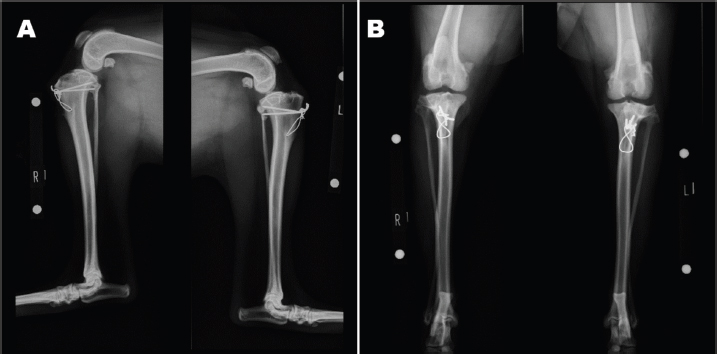

An 11-month-old intact male Siberian Husky was referred to us with the main complication reported as bilateral hind lameness and LPL, diagnosed by a family doctor. His posture showed an X-linked knee. Physiological examination showed bilateral patellar luxation with grade 4 and negative for cranial drawer sign and tibial compression test. The radiograph showed severe bilateral LPL without changes in the hip joint (Figs. 1A-B). His quadriceps (Q) angle showed right=43.37°and left=32.15°. Diazepam 0.1 mg/kg, ketamine 0.5 mg/kg, and fentanyl 5 μg/kg (intravenous), atropine 0.05 mg/kg (intramuscular), and meloxicam 0.2 mg/kg (subcutaneous) were administered as the premedication. After an induction of propofol 6 mg/kg, ropivacaine 0.22 mg/kg was used for epidural anesthesia. Under general anesthesia, the patient was immobilized in the supine position. Surgical techniques included bilateral block trochleoplasty, tibial tuberosity with tension band wiring using Kirschner wire, modified capsules (release of the lateral capsule and suturing of vastus medialis, plication), and the modified MPFL. The modified MPFL was used with the Cruciate Needle (medium, 40 lb) 40# suture (monofilament nylon) single strand (SECUROS, MA), suturing from the lateral aspect of the patella periosteum to the medial sesamoid bone (Figs. 2A-B). The postoperative radiograph is shown in Figures 3A-B. The patient has shown no luxation over 1 year after the operation.

Fig. 1. Preoperative radiograph. Severe bilateral LPL was detected.